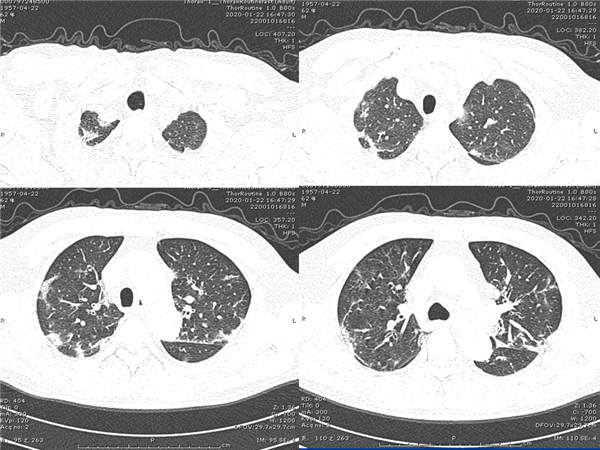

【病例分享】新型冠狀病毒感染肺部CT影像4例(常德市第一人民醫(yī)院)

幻燈片7.jpg